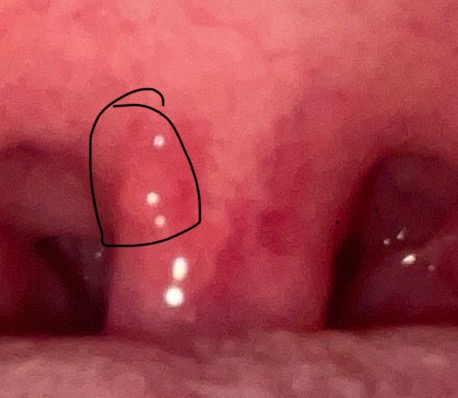

ผมเป็นตุ่มใส่ๆตรงลิ้นไก่นะครับ มันอันตรายมั้ย สอบถามผู้รู้หน่อยครับ( มีรูป )